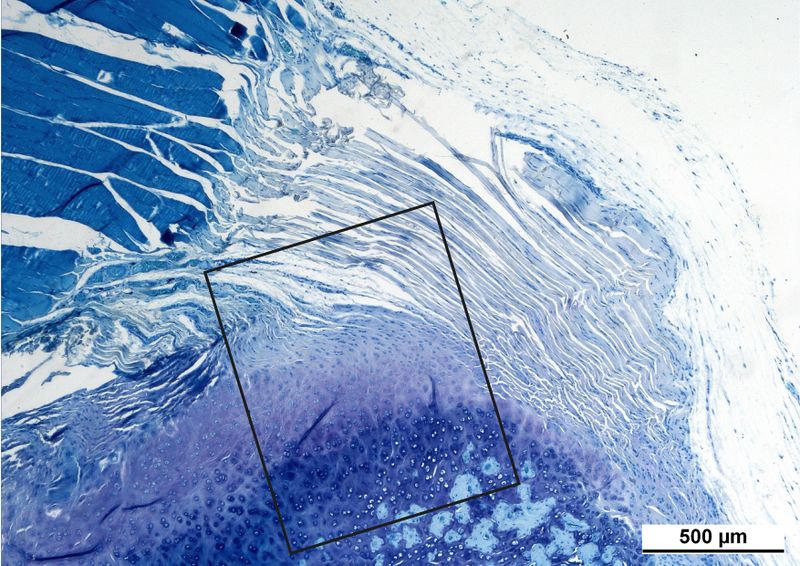

Physiologic structure of an enthesis consists of 4 zones which are visible in the left pictures (1a, 500 μm). Details of the enthesis (1b, 100 μm) with the tendon (T), the unmineralized fibrocartilage (FC) the mineralized fibrocartilage (cFC) and the bone.